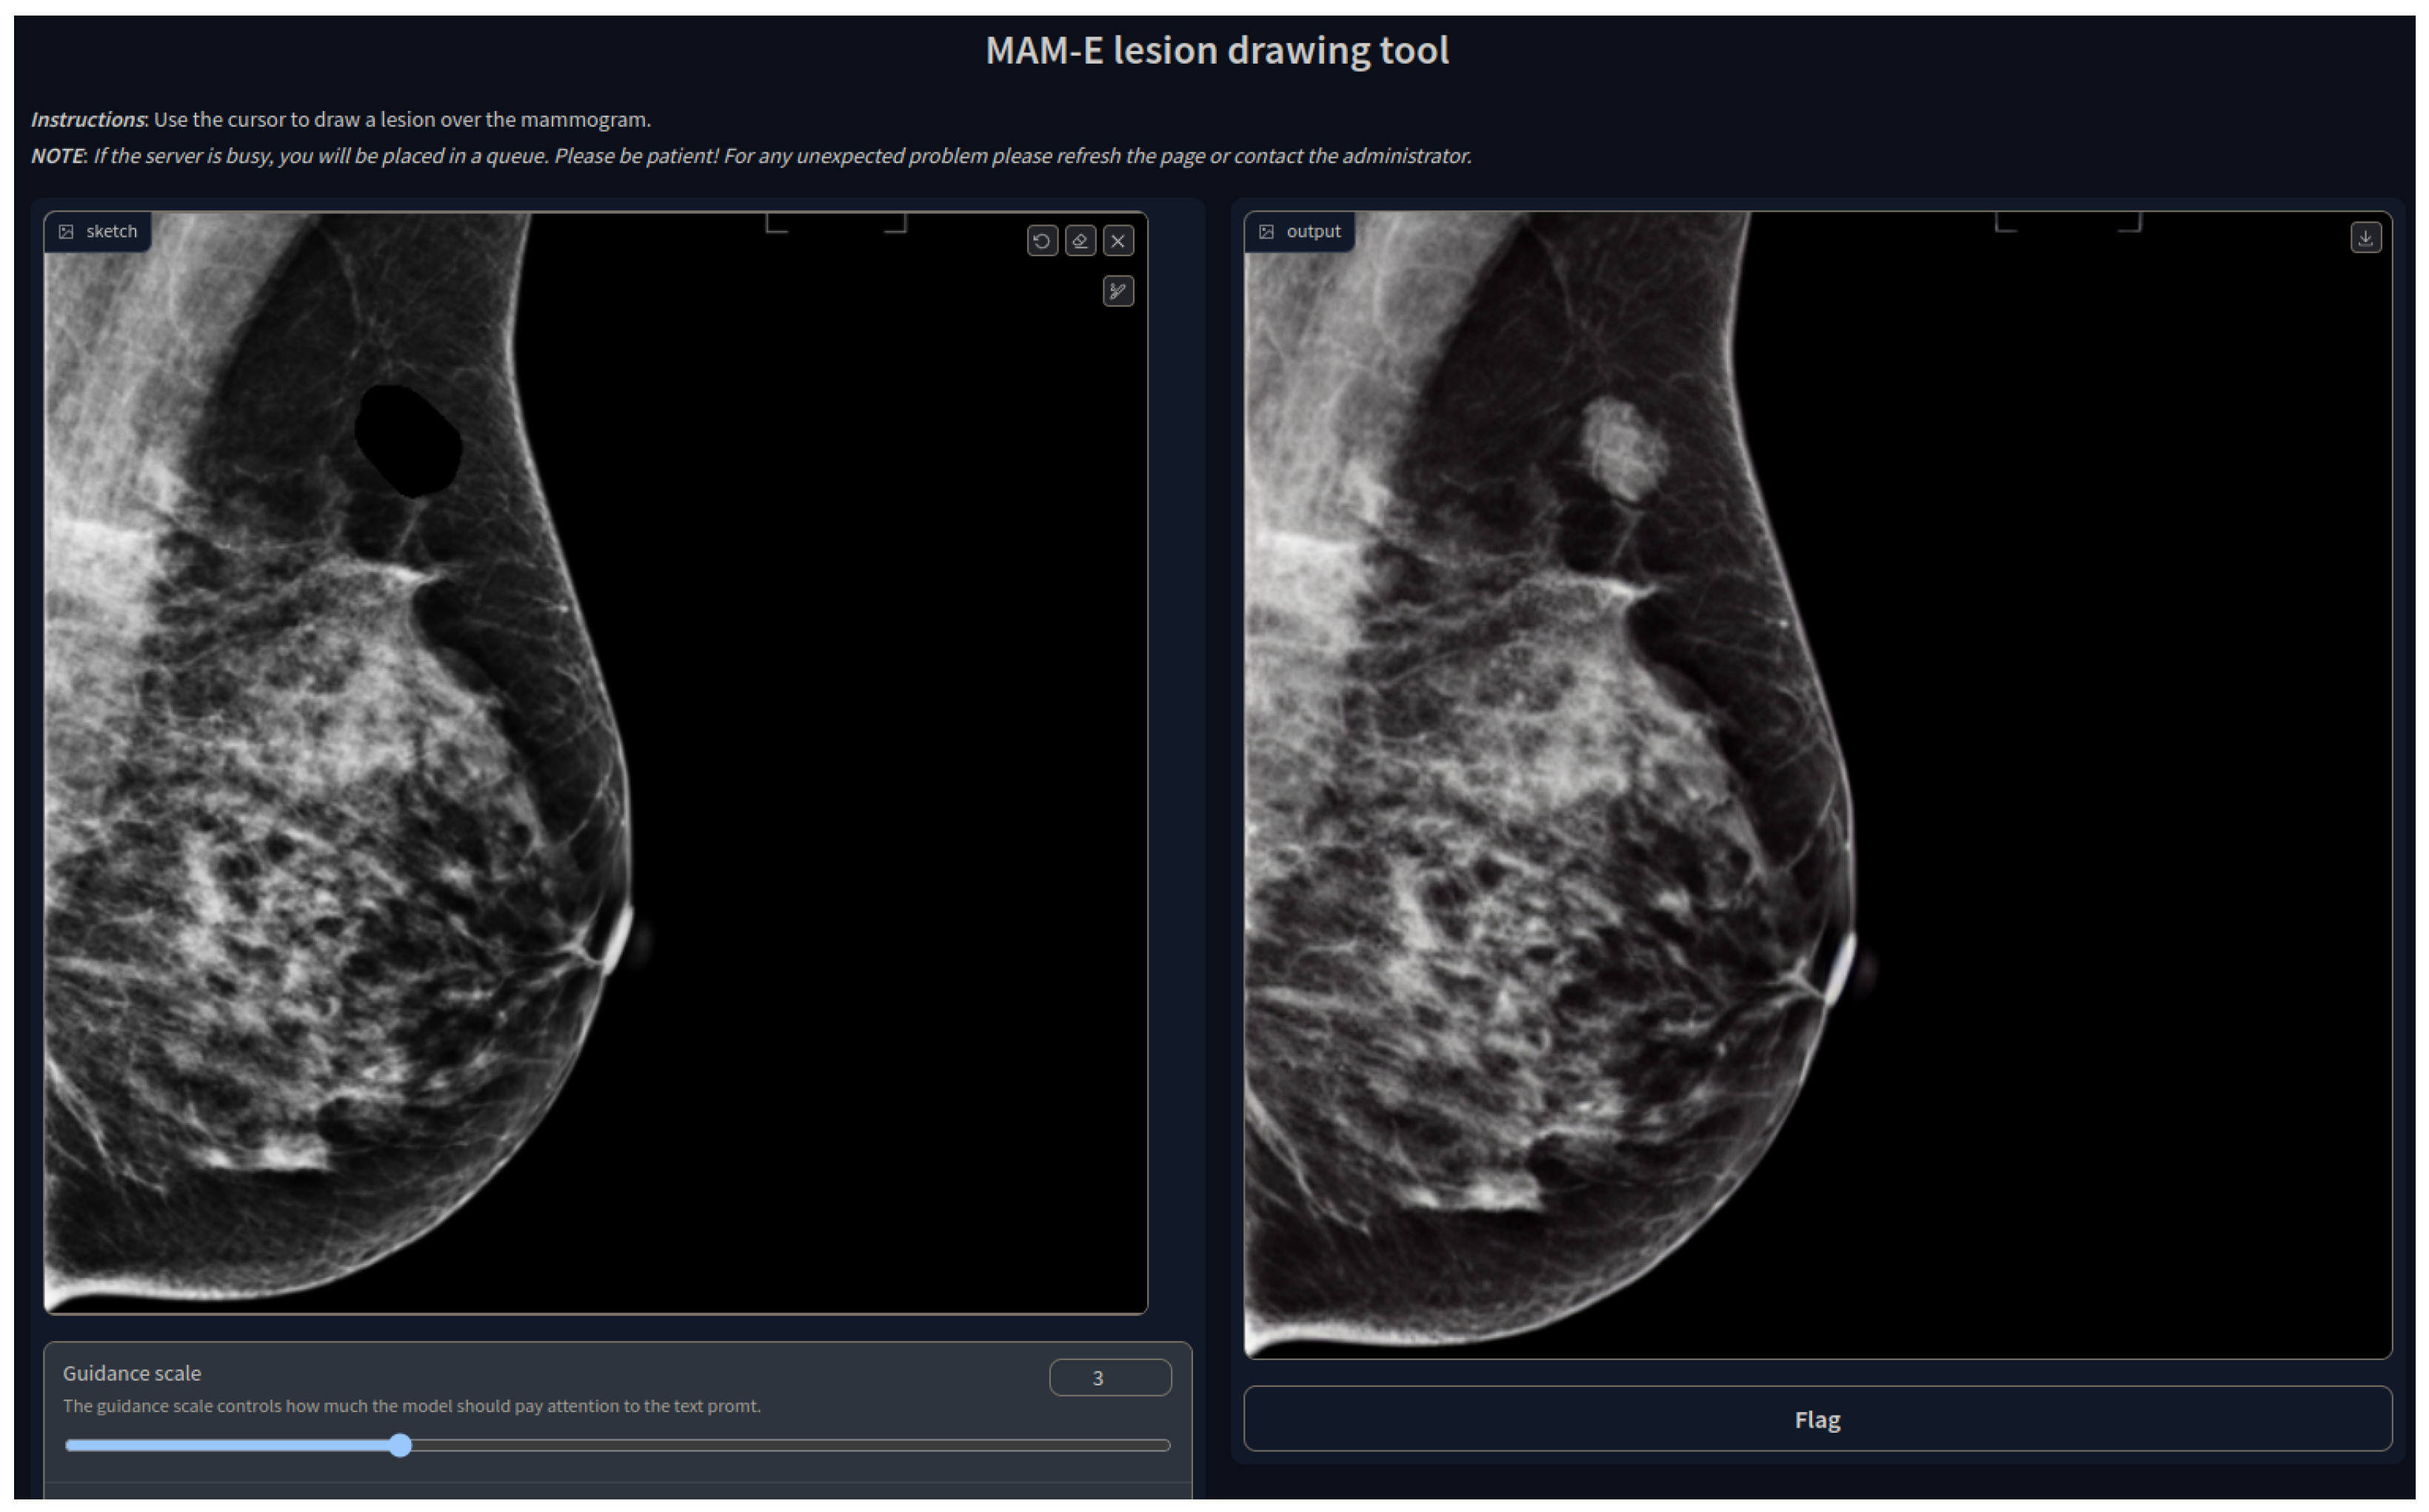

This work source code publication is the first implementation of SD for mammographic image generation and can be found at https://github.com/VICTORIA-project/mam-e (accessed on 21 March 2024), along with the pretrained weights at https://huggingface.co/Likalto4 (accessed on 21 March 2024). Additionally, graphical user interfaces for both synthesis tasks were designed, as shown in Figure 1, for easy-to-use image generation.

Figure 1.

Graphical user interface of MAM-E for generation of synthetic healthy mammograms.

3.3. MAM-E Graphical User Interfaces

We decided to build GUIs to make the pipelines of both tasks available to the public and easy to use. Our GUIs can run on remote servers and be accessible on the web thanks to GradIO, an open-source Python package for the rapid generation of the visual interface of ML models, by [36].

We developed five GUIs, one for each of our main diffusion pipelines. Two were designed for the conditional generation of mammograms of the original Siemens and Hologic datasets separately, with their own prompt characteristics. Similarly, one pipeline was created for the combination of both datasets, and it is presented as an example in Figure 1. In these three cases, the personalization options are set fixed and the user can only pick from the available options. Nevertheless, we added the option of a negative prompt, which allows the user to further personalize the generation.

The idea of the negative prompt is to specify some features that the user would like to be avoided. For instance, in the cases when a synthetic image presents a gray or white background, a negative prompt of “white background” or “no black background” has been shown to make the background black.

In the case of the inpainting task, the GUI has the option to upload the image that will be inpainted, although a default image is available. An interactive drawing brush is then activated, with which a lesion can be inpainted in any part of the mammogram, as shown in Figure 19.

Figure 19.

MAM-E lesion drawing tool.